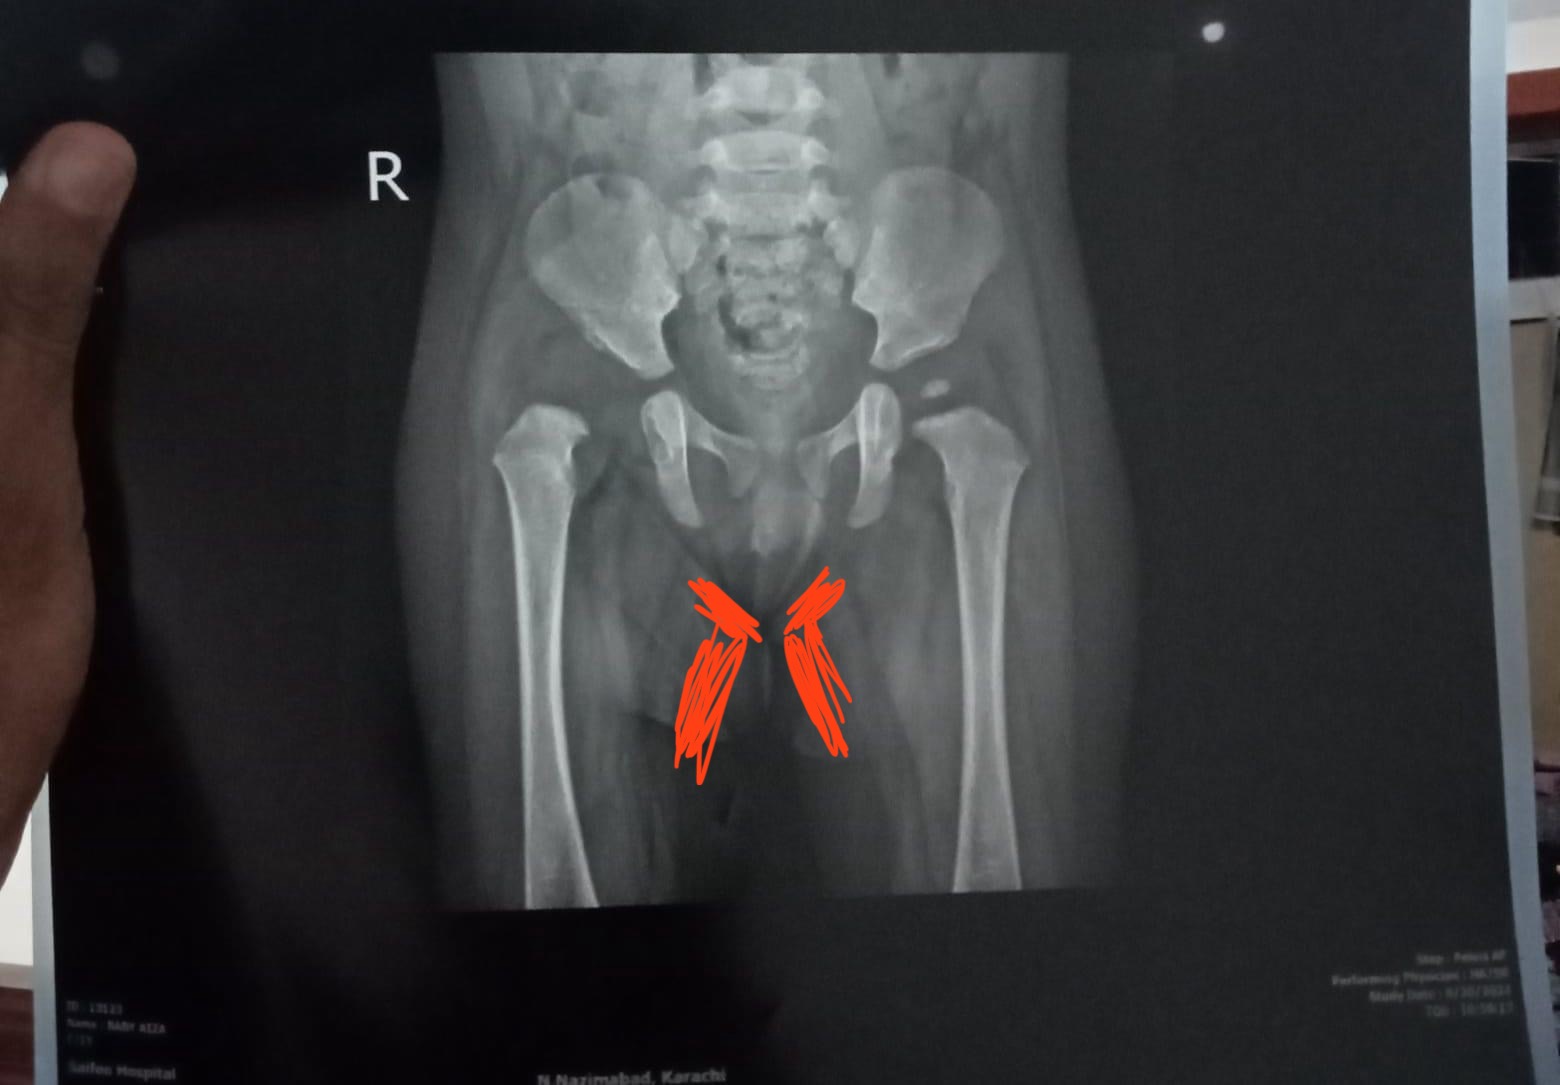

Asking for Self, Male, 29 years old, Karachi

Assalam o Alaikum, I need to discuss a severe situation which is getting me into depression.

I’ve noticed the area between my legs (upper thighs) and my hips is getting darker and doesn’t match my actual skin tone. The skin on the highlighted area has become very sensitive as well and gets itchy at times.

Since last couple of months my pelvic region got too much rashes (especially ballsack) and it gets smelly which i can’t stop thinking about.

PS: Picture is posted just for the reference. Thanks